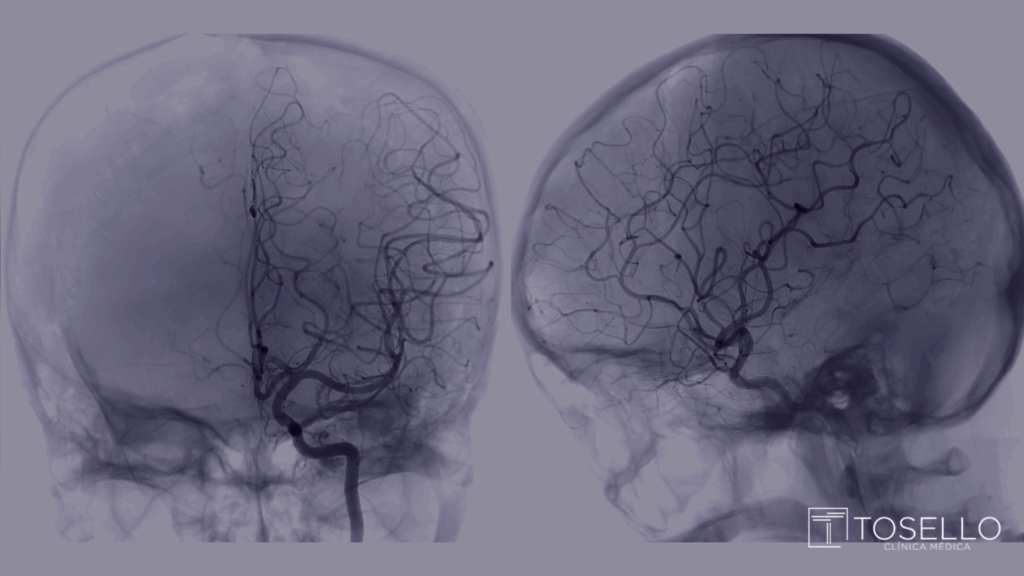

A embolização é um tratamento minimamente invasivo realizado por meio da neurorradiologia intervencionista. Nela, um cateter é inserido por uma artéria da virilha ou do punho e, guiado por imagens, é levado até o aneurisma. Pequenas molas metálicas chamadas coils (ou outros dispositivos como stents) são inseridas dentro do aneurisma para interromper o fluxo sanguíneo e impedir que ele se rompa.